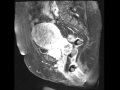

Endometrial cancer snap shots

Endometrial cancer staging tnm classification for. Endometrial cancer learn about the signs and symptoms, diagnosis, and treatment of this uterine cancer that occurs most often in women after menopause.